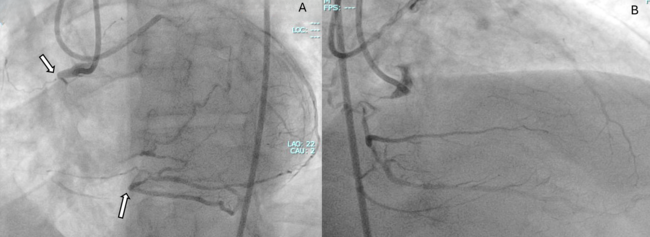

A primary retrograde strategy was selected but septal collateral wiring was unsuccessful. Epicardial collaterals from the LAD were subsequently crossed (Figure 2, Video 2); however, a retrograde wire (Confianza Pro 12; ASAHI INTECC) failed to puncture the distal cap. Antegrade wire (Gladius MG; ASAHI INTEC) knuckle was used until just before it reached the distal cap (Figure 3, Videos 3 and 4). A 3.0 x 20-mm TREK balloon (Abbott) was delivered retrogradely through the epicardial collateral and inflated at the bifurcation (Video 5). Next, an antegrade wire (Gladius EX; ASAHI INTECC) was delivered into the distal true lumen of the posterior descending artery (Figure 4, Video 6). The RCA was successfully stented with an XIENCE Pro drug-eluting stent (Abbott), with restoration of Thrombolysis in Myocardial Infarction 3 flow (Figure 5, Video 7).